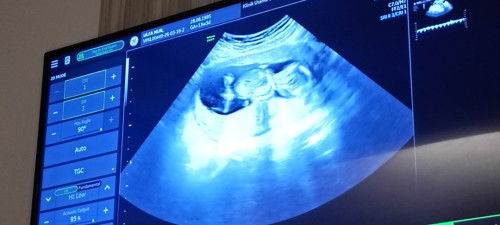

Foto USG 13 minggu

ini kak 13 minggu 4 hari...